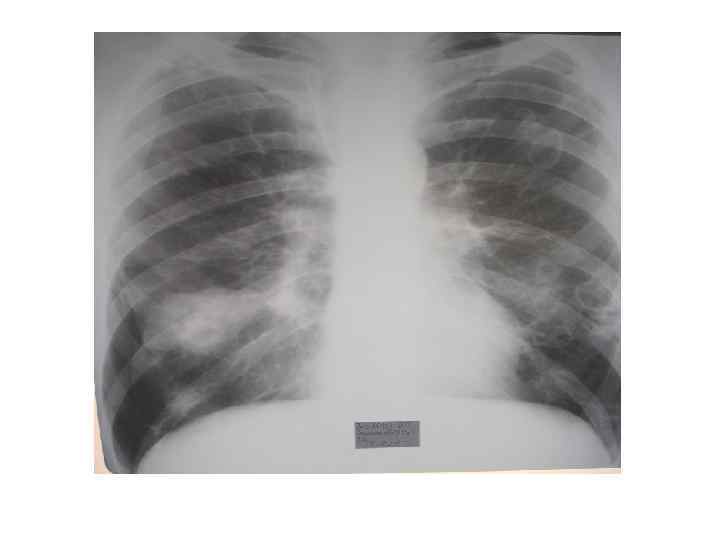

Рентгенологические признаки СЭЛА при ИЭ • двустороннее поражение; • наличие множественных небольших, нечетких округлых или овальных теней различных размеров (у 68% ), очаговых инфильтратов (у 54%) и клиновидных теней (у 22%) расположенных чаще всего в периферических зонах легких или субплеврально; • склонность к распаду инфильтратов с возникновением абсцессоподобных полостей (у 50%) и кист (у 81%); • быстрая динамика появления новых инфильтратов и медленное обратное развитие с длительным сохранением кистовидных тонкостенных полостей; • возможно развитие плеврального выпота (у 50%) и редко пиопневмоторакса. По данным Zuo LE, Guo S. (2007)

Рентгенограмма легких при рецидивирующей септической эмболии легочной артерии у больного трикуспидальным ИЭ

Руководство по ИЭ Европейского общества кардиологов 2004: Множественные быстро меняющиеся легочные инфильтраты вызывают подозрение на ИЭ правых отделов сердца